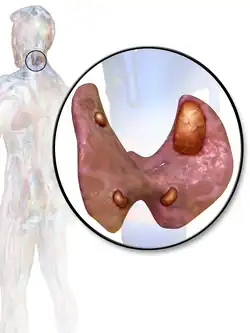

A human being usually has four parathyroid glands located on the posterior surface of the thyroid in the neck. In order to maintain calcium metabolism, the parathyroid glands secrete parathyroid hormone (PTH) which stimulates the bones to release calcium and the kidneys to reabsorb it from the urine into the blood, thereby increasing its serum level. The action of calcitonin opposes PTH. When a parathyroid adenoma causes hyperparathyroidism, more parathyroid hormone is secreted, causing the calcium concentration of the blood to rise, resulting in hypercalcemia.[2]